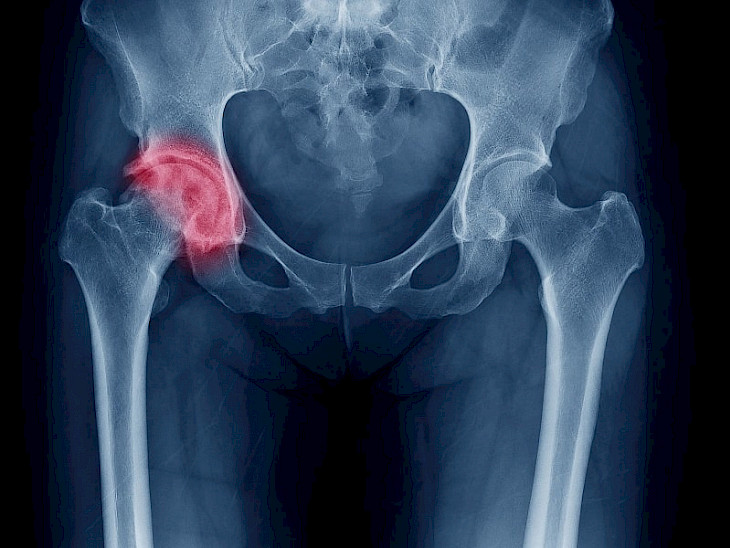

— Бул оору көбүнесе кайсы муундарды жабыркатат?

— Артроз тизе, жамбаш, чыканак, ийин муундарын жабыркатат. Айрыкча тизе муунунун артрозго чалдыккан учурлары абдан көп.